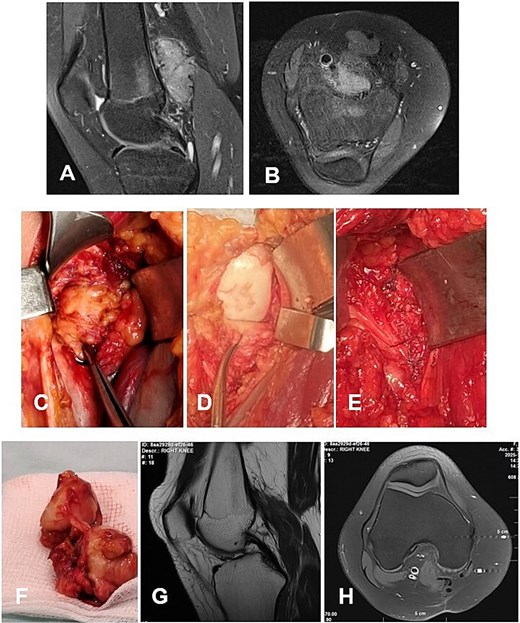

А 16-year-old female athlete presented with knee effusion and pain without preceding trauma, persisting for 3 months. Diagnostic MRI revealed an intra-articular, retrocondylar mass with intact cruciate ligaments and menisci (Fig. 6A and B). The lesion was identified as a nodular tenosynovial giant cell tumor and was excised through a posterior partial synovectomy using a medial approach with lateral retraction of the m. gastrocnemius medialis. The tumor was removed sharply and en bloc within macroscopically healthy synovial margins (Fig. 6C–E). At the 12-month postoperative follow-up, the patient was asymptomatic, with no MRI evidence of local recurrence (Fig. 6F and G). Successful return to full athletic activity.

Case 5. (A and B) Preoperative sag and ax MRI TSE PD FS—lobulated edematosus intra-articular neoplasm with a posterior mediocentral localization. (C and D) Posterior synovectomy between m. semitendinosus and m. gastrognemius medialis. (Е) Macroscopic appearance of the N-TGCT measuring 3 × 2 × 2 cm after excision. (F and G) Postoperative 12 m. Sag and Ax MRI TSE PD FS—no evidence of recurrence of the resected neoplasm. PD FS, proton density weighting with fat suppression; TSE, turbo spin echo.